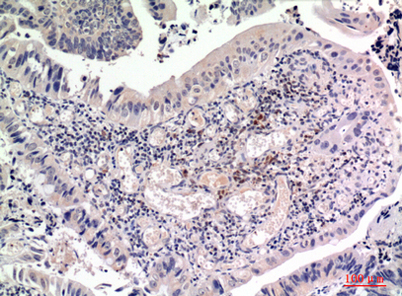

Product name: FGF-2 rabbit pAb

Dilutions: Western Blot: 1/500 - 1/2000. IHC-p: 1:100-1:300. ELISA: 1/10000. Not yet tested in other applications.

Immunogen: The antiserum was produced against synthesized peptide derived from the Internal region of human FGF2. AA range:151-200